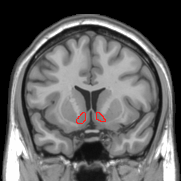

Look At Those Cute Nucleus Accubens

When you engage in social interaction, oxytocin neurons in the paraventricular nucleus of your hypothalamus fire rapidly, releasing oxytocin into the ventral tegmental area—a key node in the brain's reward circuitry.